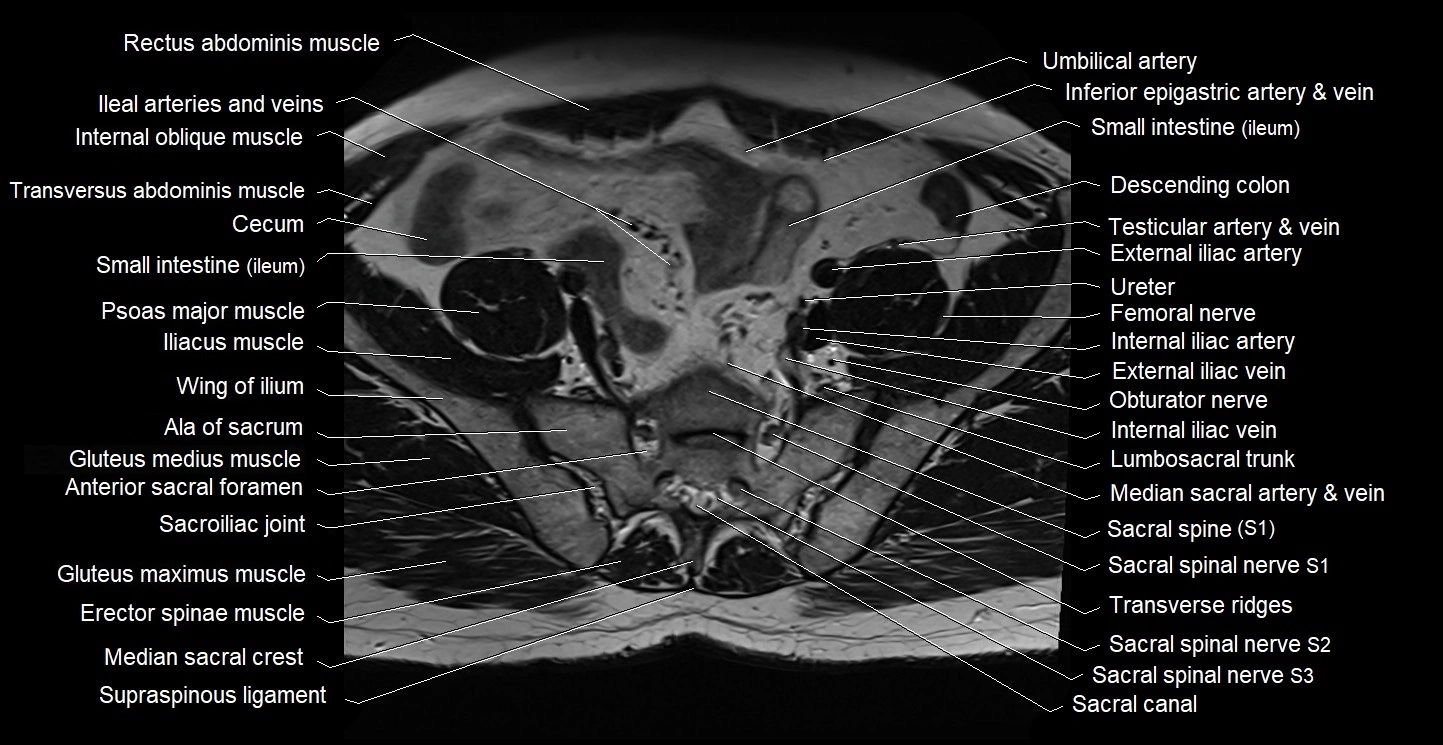

- Ala of sacrum

- Anterior sacral foramina

- Cecum

- Erector spinae muscles

- Gluteus medius muscle

- Intermediate sacral crest

- Lumbosacral trunk

- Median sacral crest

- Posterior sacral foramina

- Sacral canal

- Sacroiliac joint

- Transverse ridges